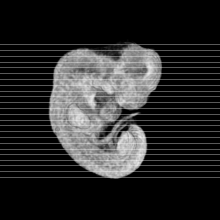

Human Embryo

Carnegie Stage 15 (33 post-ovulatory days)

Most embryos at stage 15 are approximately 33 postovulatory days old and measure 7-9 mm in length. Distinguishing criteria for this stage include the appearance of nasal pits and hand plates. The lens vesicles are closed.